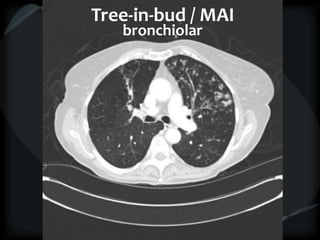

Tree-in-Bud Appearance

Bronchiolitis

Rare- tumor cell emboli – intralobular artery

Tree-in-bud / MAI

bronchiolar

Bronchiolitis - MTB

Subacute HP

bronch / peribronch / gg

RBILD

Avium / DPB